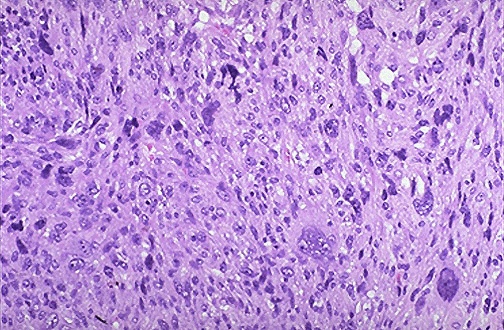

Cellular morphology of sarcoma

Nuclear feature of sarcoma cells

Differentiation status of sarcoma cells

Pleomorphic cells vary in size and shape

Hyperchromatic nuclei

Poorly differentiated or anaplastic